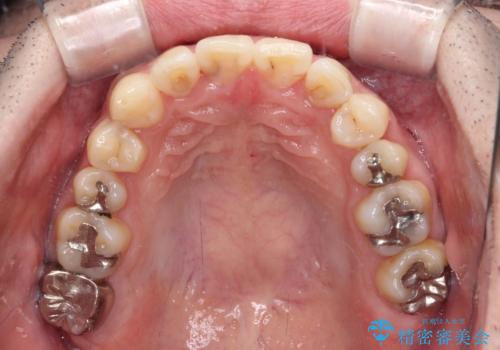

- デコボコした前歯をセラミックできれいに揃えたいとのことで来院された患者様です。

歯を削って整えることは簡単ですが、健全な歯を削って後悔してからでは遅いため、矯正治療を提案しました。

はじめは矯正治療の期間が長いことに悩んでいらっしゃいましたが、ある程度整えば満足するだろうとのことで、インビザラインにて矯正治療を行うこととしました。

左上の犬歯が欠損しているため、正中の位置や奥歯の咬み合わせが理想的にならない点を了承していただきました。

インビザライン矯正は、1日22時間を目安に装着する必要がありますが、しっかりと装着してくださったので、順調に治療を進めることができました。